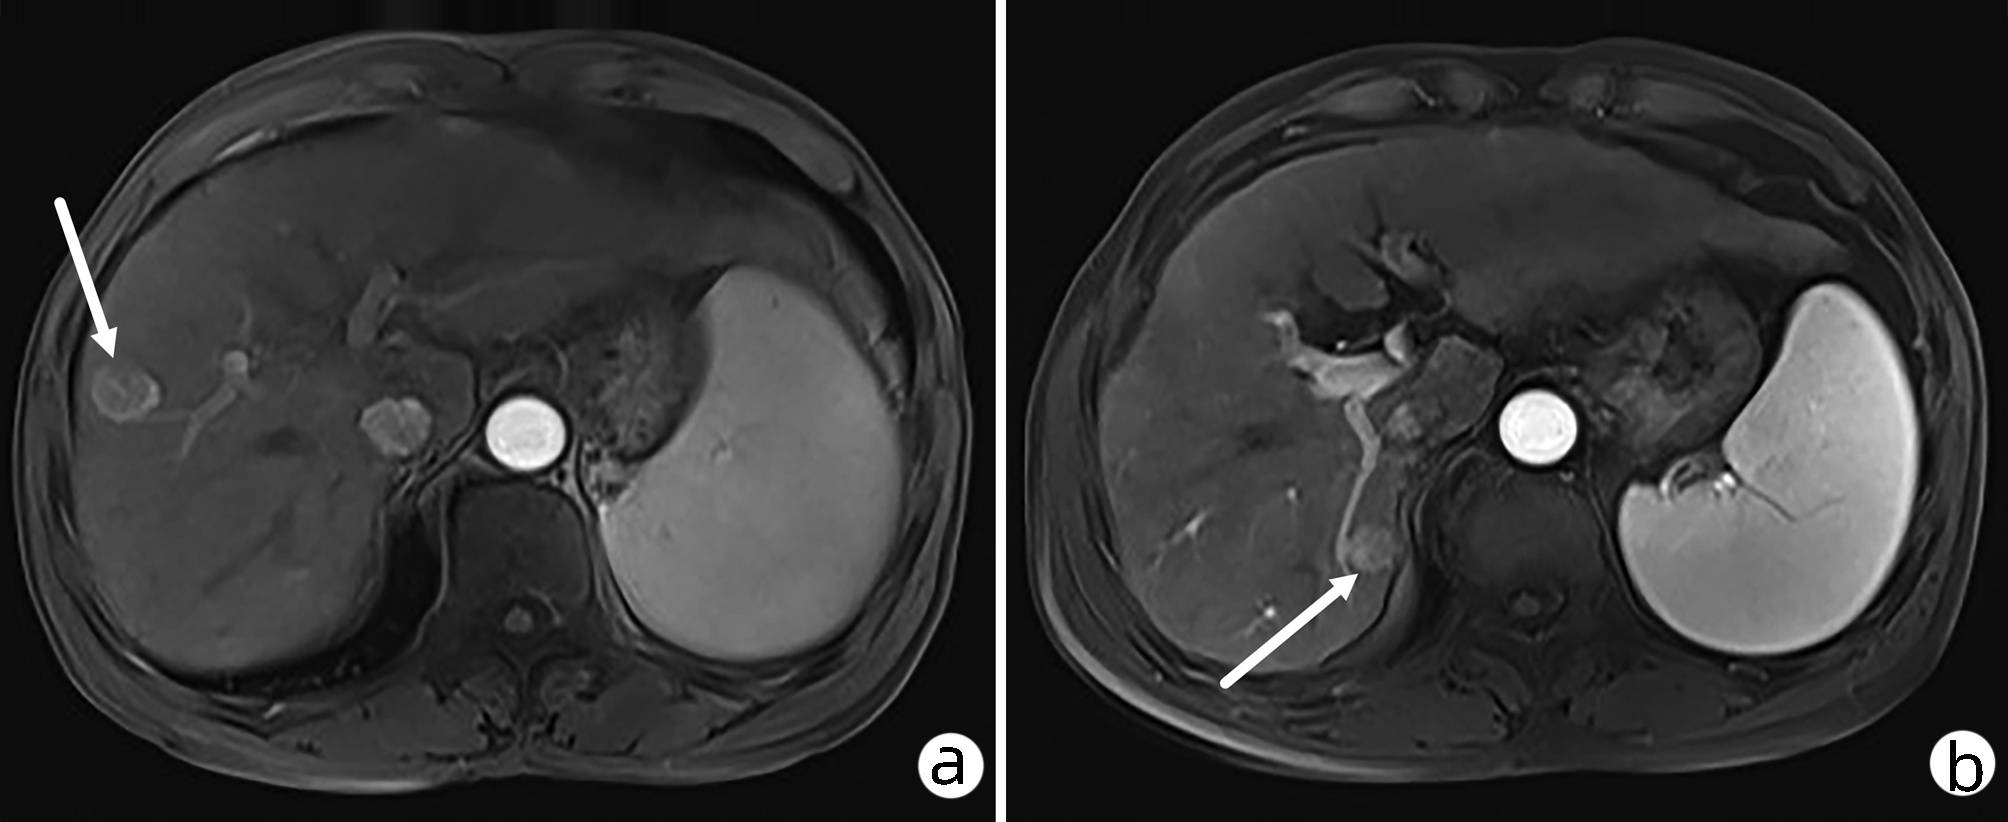

Schwannoma of the pancreatic tail: A case report

Jiachao ZHANG, Rong TANG, Zhensheng ZHANG, Pingping CHEN, Yongchao ZENG

2022, 38(8): 1878-1879. DOI: 10.3969/j.issn.1001-5256.2022.08.030

Abstract(685) HTML (278) PDF (3067KB)(72)

Abstract: